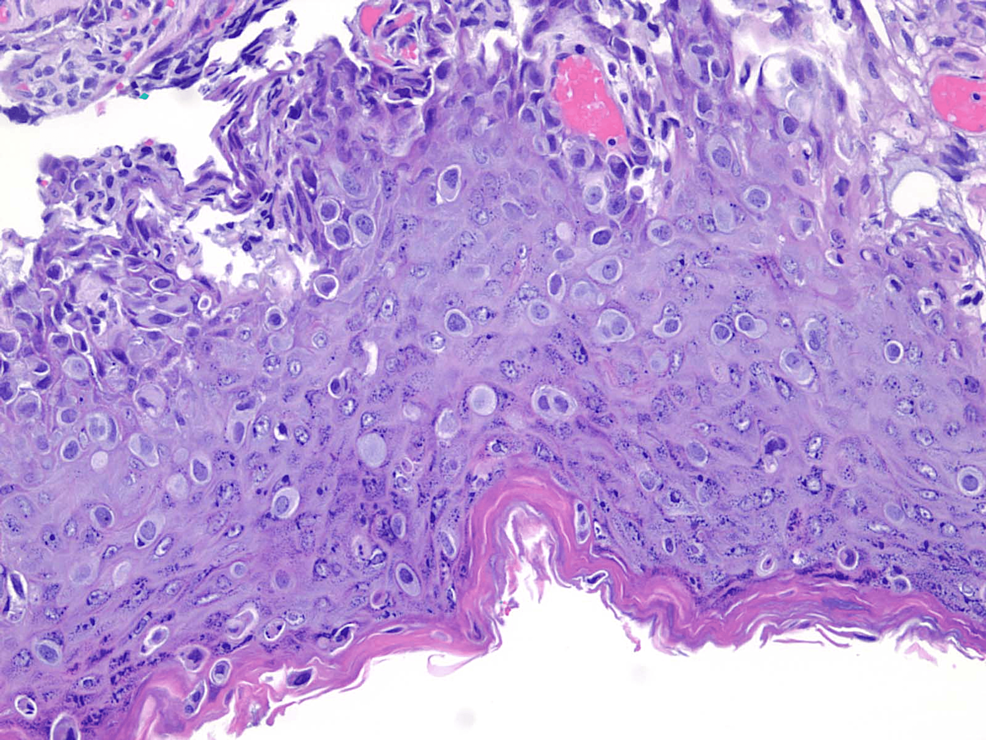

Paget Disease of the Breast Mammographic, US, and MR Imaging Findings with Pathologic